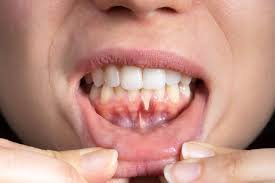

Periodontal Treatment - Gum Disease

Gum Disease is the most prevalent dental condition in the human mouth. We see more and more patients suffering from Periodontitis. It is silent  and discrete and can go unnoticed for years and sometimes decades like termites in cabinetry. One of the early signs of gum disease is bleeding gums upon tooth brushing and bad breath.

If left untreated Periodontitis will result in the loosening and eventual loss teeth . Gum Disease is the primary cause of Adult tooth loss.

At all our centres we diagnose and treat Periodontal disease when the progress is within our scope. Advanced Periodontitis will be referred to a Specialist Periodontist in Perth.